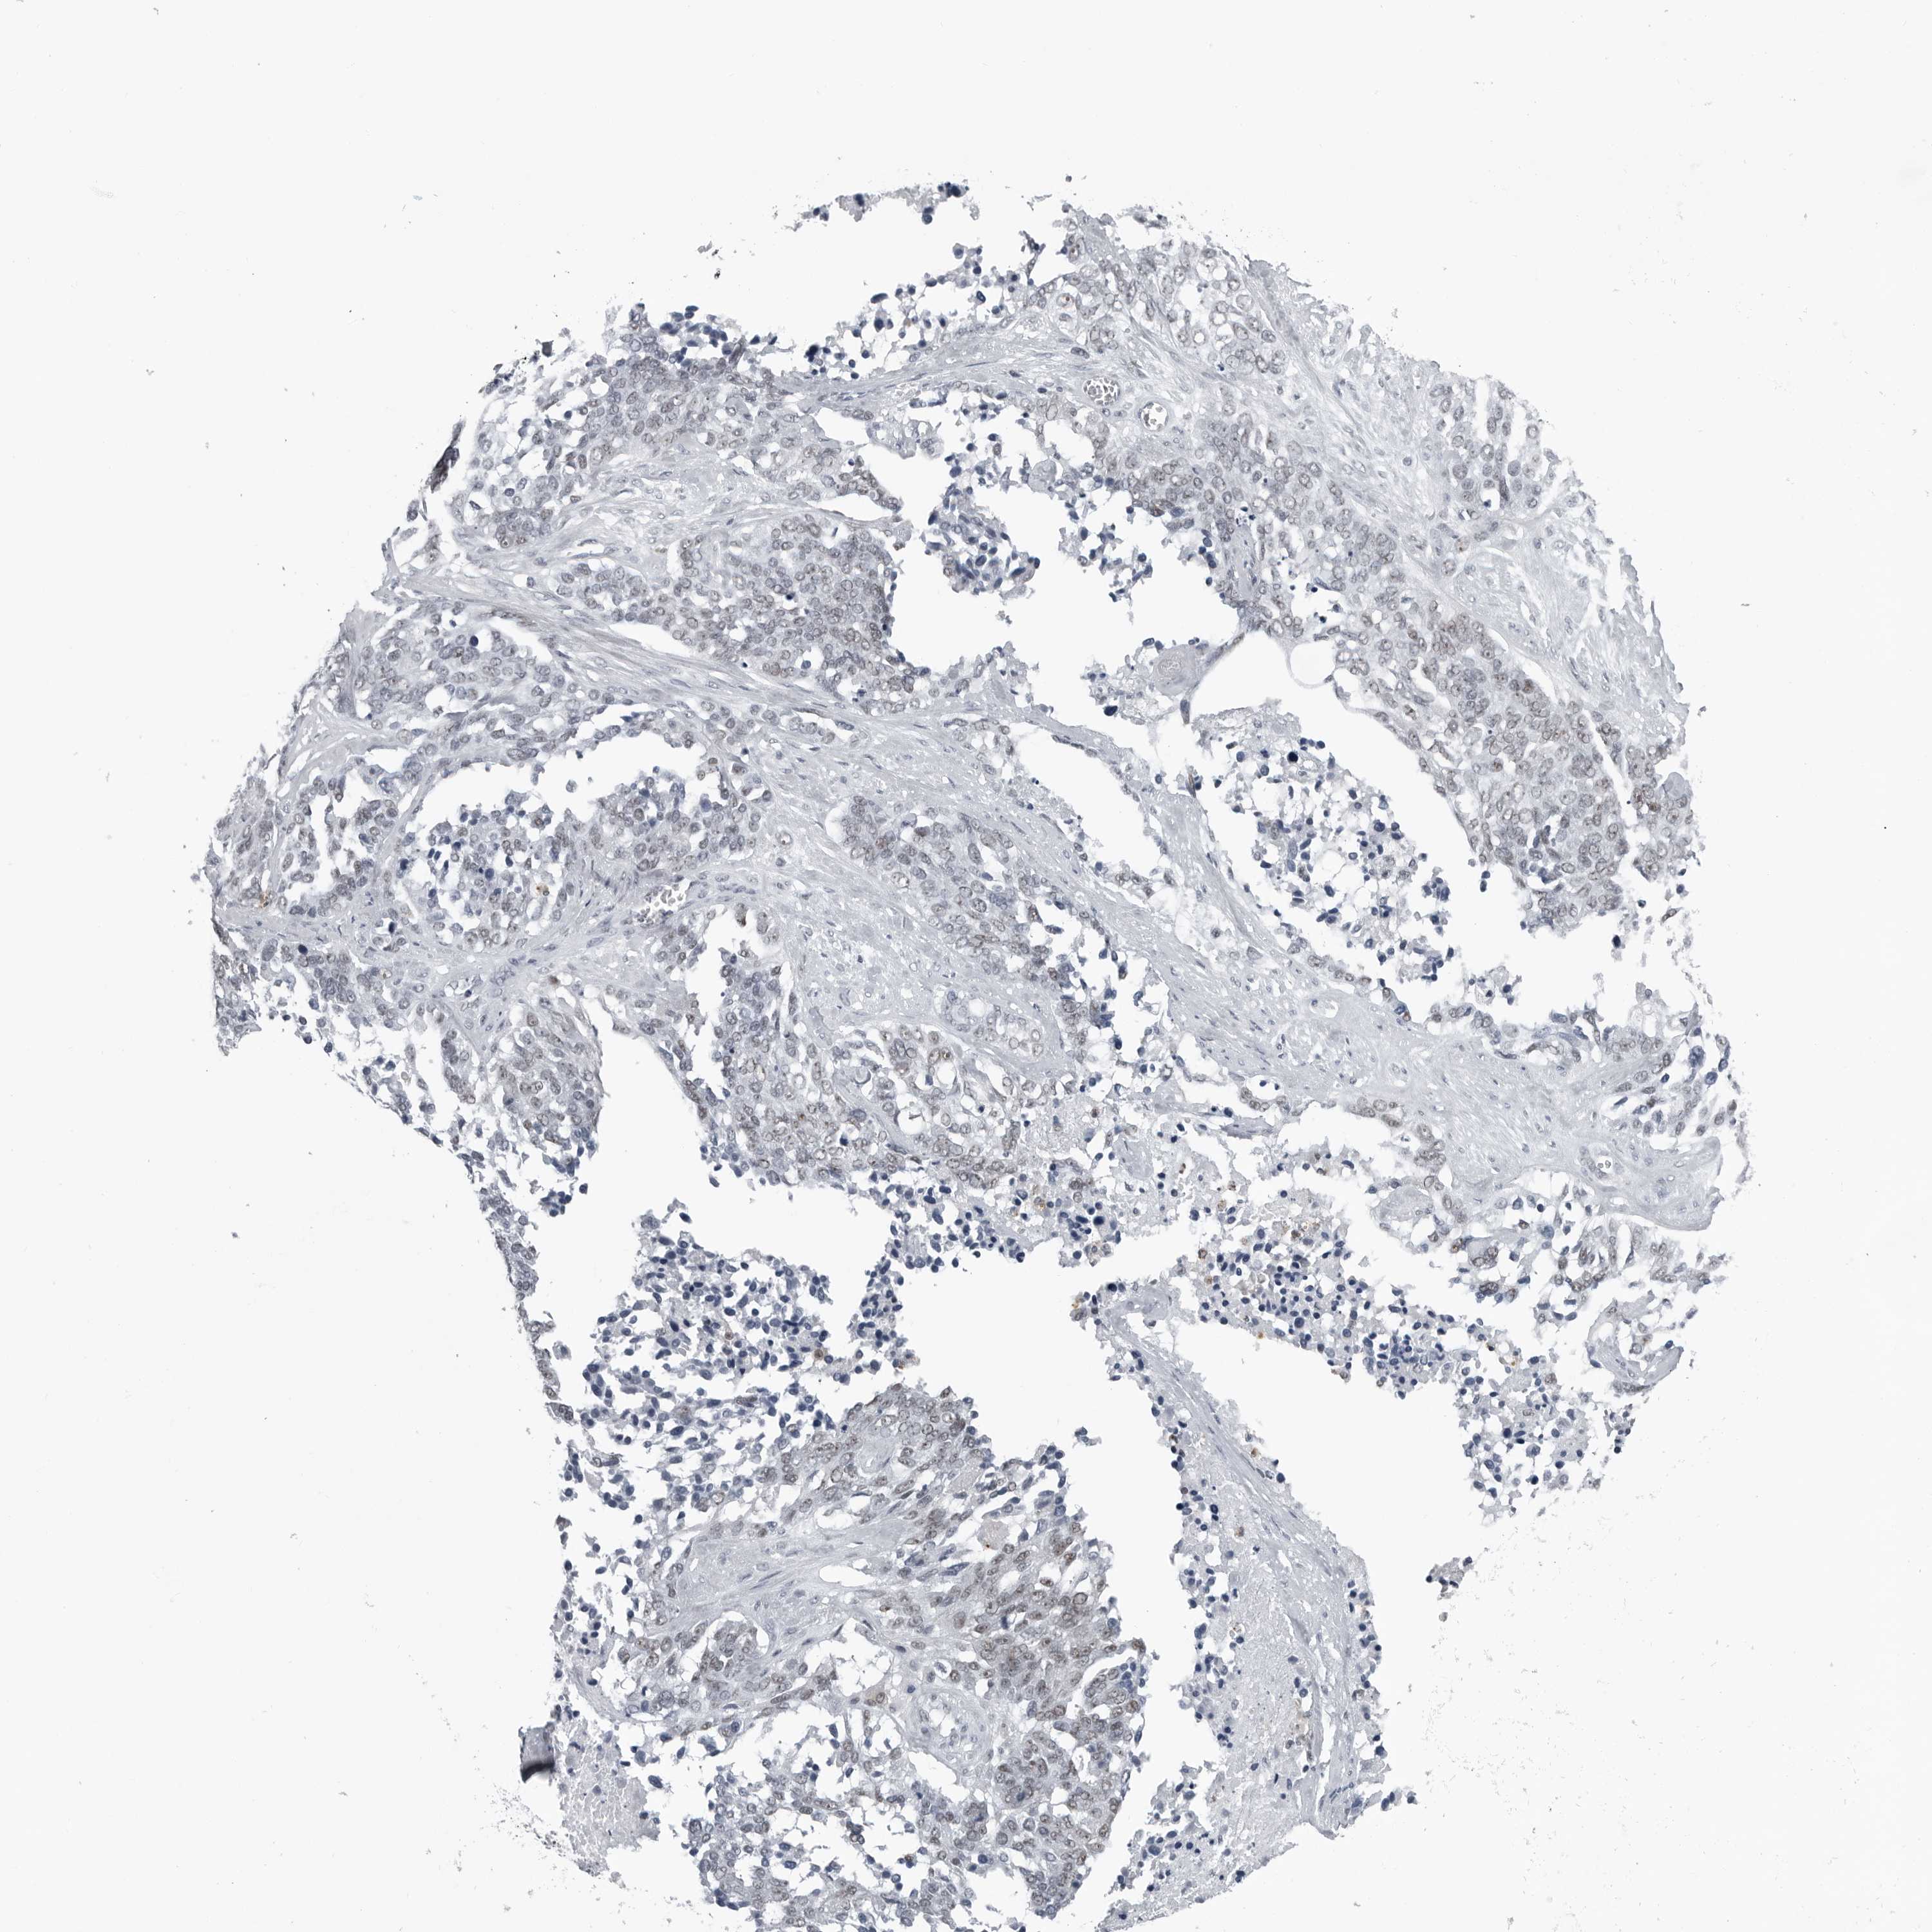

OVARIAN CANCER - Protein expressioni

A mouse-over function shows sample information and annotation data. Click on an image to view it in a full screen mode. Samples can be filtered based on level of antibody staining by selecting one or several of the following categories: high, medium, low and not detected. The assay and annotation is described here.

Note that samples used for immunohistochemistry by the Human Protein Atlas do not correspond to samples in the TCGA dataset.

Antibody stainingi

Antibody staining in the annotated cell types in the current human tissue is reported as not detected, low, medium, or high, based on conventional immunohistochemistry profiling in selected tissues. This score is based on the combination of the staining intensity and fraction of stained cells.

Each image is clickable and will lead to virtual microscopy that enables deeper exploration of all samples and also displays staining intensity scores, fraction scores and subcellular localization as well as patient and tissue information for each sample.

Antibody CAB006246

High

Medium

Low

Not detected

Carcinoma, NOS